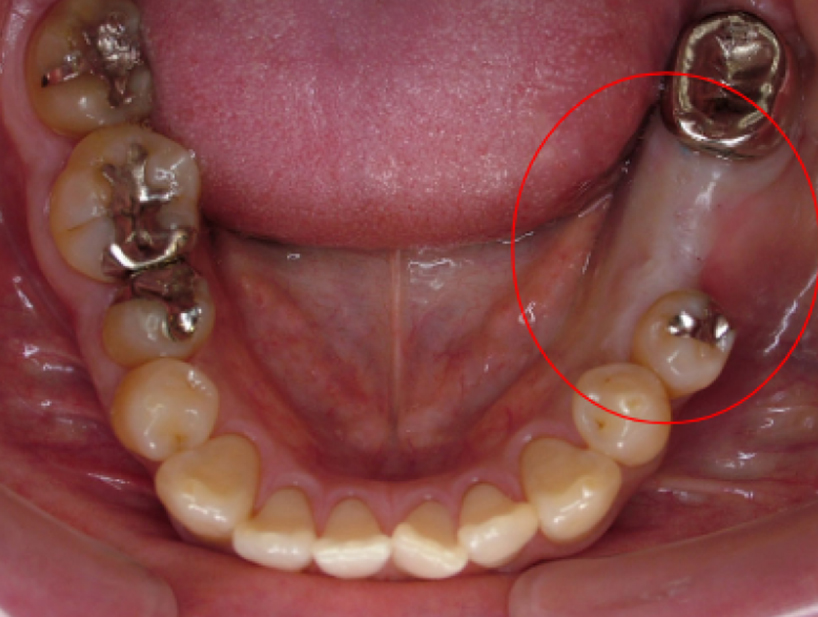

治療前治療後

| 治療内容 | インプラント奥歯1本・根管治療・矯正治療(圧下) |

|---|---|

| 患者様の年齢 | 40歳 |

| 患者様の性別 | 男性 |

| 治療期間 | 1年 |

| 治療回数 | 矯正治療合わせて50回程度 |

| 治療費用 | 根管治療1歯6万円/インプラント治療1歯50万円 矯正治療:1歯 10万円 |